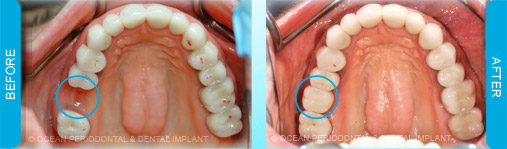

Dental implants are commonly used to replace missing or lost teeth in order to ensure patient comfort, function, and aesthetics. Indeed, there are many treatment options for management of missing teeth, such as bridges, and partial/complete dentures.

Nonetheless, numerous studies have demonstrated that implant-supported restorations are generally deemed to have superior functional and aesthetic outcomes. Furthermore, there are cases where dental implants may be the only logical choice for the restoration of function and aesthetics.

Dental implants can be used to replace missing teeth. There are many benefits to this type of treatment.